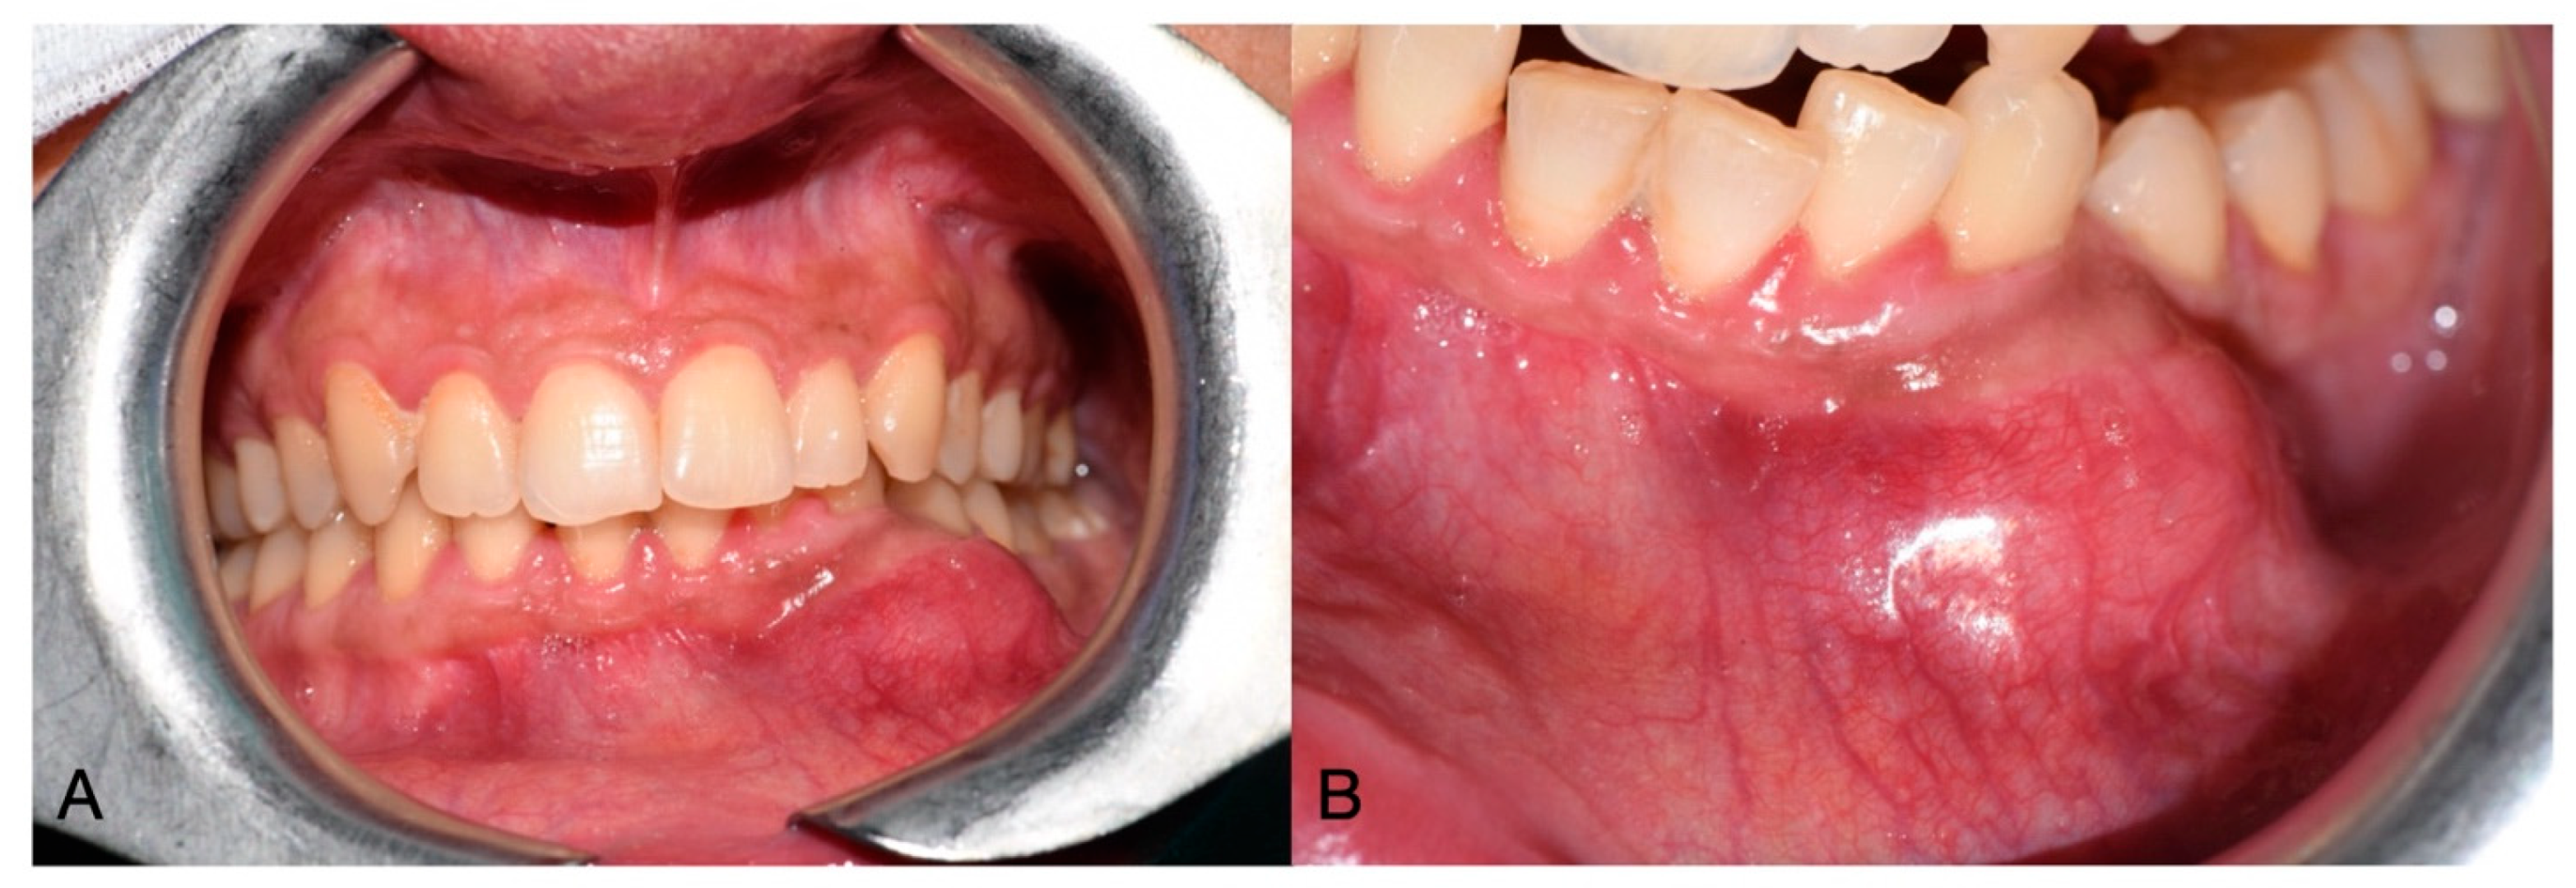

A 44-year-old female patient presented to the Oral Surgery department of the University Hospital of Pisa with a swelling in the left lower jaw, seeking specialist medical advice. The intraoral examination revealed a raised, painless, and tender-at-palpation mass in the buccal vestibular area of the lower left mandible, extending into the labial region, with normal color and the appearance of the surrounding mucosa (Figure 1).

Figure 1.

Clinical initial situation in frontal vision (A), and close-up view of the lesion (B).